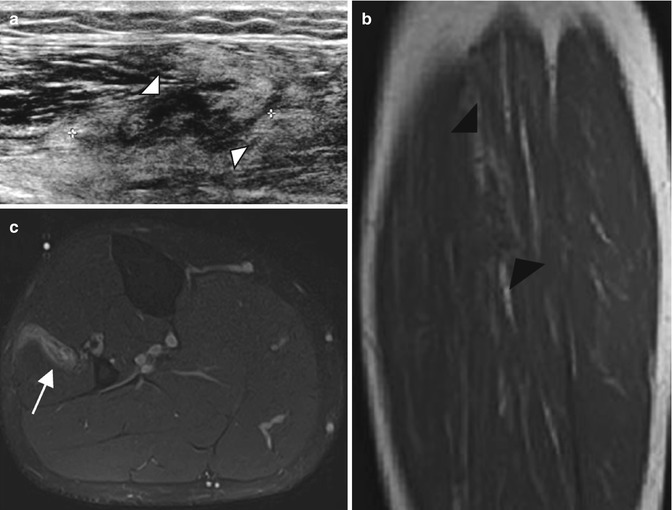

Stewart-Treves syndrome in a 66-year-old woman who was treated 20 years ago for uterus cervical cancer. (a) Axial T2-weighted MR image, with fat suppression. (b) Axial T1-weighted MR image. (c) Axial T1-weighted MR image after Gadolinium contrast administration, with fat suppression. (d) Clinical photograph. (a) Axial T2-W fat-suppressed MR images reveals an enlarged right extremity with subcutaneous edema (arrowheads) (a–c) Nodular mass of low signal intensity on T1, with low to intermediate and heterogeneous signal intensity on T2 and a heterogeneous enhancement (arrows) representing the angiosarcoma. (d) Clinical photograph shows the purplish skin lesion